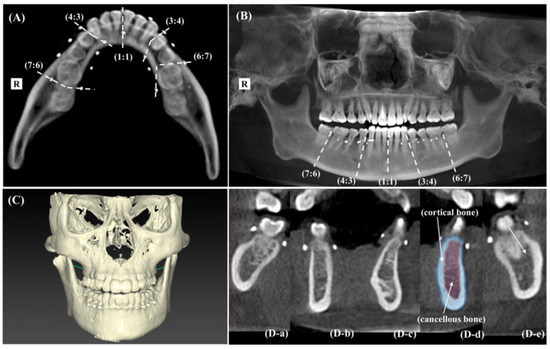

2.6.3. Bone Resorption Marker